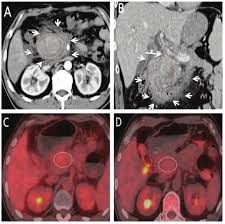

Unknown masses in the liver, pancreas or kidneys can be identified as tumors or not. Like the other 3 tests in this group, the ct scan is painless. A ct takes, on average, less than 60 seconds while an abdominal mri takes closer to 30 minutes. Abdomen pain and suspicion, should i get a ct scan or mri? answered by a verified doctor: A general surgeon does not necessarily mean you need surgery, but their training makes them experts in abd pains. Cat scans, mri scans, ultrasound, and mibg are shown and described. An mri is suited for examining soft tissue in ligament and tendon injuries, spinal cord injuries, brain tumors, etc. Pet scans provide metabolic information and are increasingly read alongside ct or mri (magnetic resonance imaging) scans, which provide anatomic information.